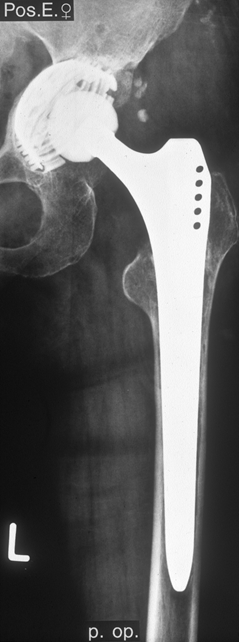

Fallbeispiel

Weiblich, 55 Jahre. Es zeigt sich eine schwere Dysplasiearthrose der

rechten Hüfte (links im Bild) sowie eine Subluxation des linken Hüftkopfes mit

partiellem Kopfeinbruch.

Beide

Hüftgelenke wurden in einer Operation ersetzt. Das Röntgen zeigt das

Ergebnis 10 Jahre postoperativ. Beide Hüften sind stabil im Knochen

verankert, die Patientin ist außerordentlich zufrieden.